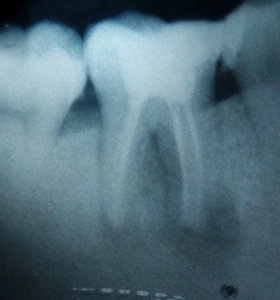

Я пошла в поликлинику с острой зубной болью. Мне запломбировали каналы и поставили временную пломбу, я сильно заболела и поэтому долго с ней проходила. Сейчас пошла в платную поликлинику долечивать этот зуб. Сделали снимок, сказали, что каналы были плохо запломбированы и что там началось воспаление корней. Внешне нет никаких опухолей. Сказали удалять зуб.

Пожалуй, соглашусь с докторами из второй клиники.

На одном из корней имеется большой очаг воспаления, а также не совсем понятна ситуация в месте бифуркации (раздвоении) корней.

Зуб придется удалить.